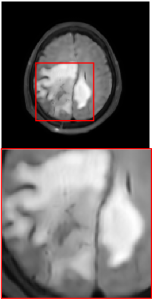

Figure 5 provides the qualitative comparison of the various methods on the four datasets at a scale of 4. The top, second, third, and bottom rows are the SR results under the FastMRI, clinical brain, clinical tumor and clinical pelvic datasets, respectively. The red boxes indicate the zoom-in region of complicated anatomical structures along with their corresponding error maps. Note that the brighter textures in the error maps, the lower the quality of the reconstructed images. As can be seen, compared to methods based on Transformers and CNNs, diffusion-based methods like DisC-Diff and DiffMSR (Ours) are capable of reconstructing high-realistic images with promising reconstruction metric scores (PSNR and SSIM). Nevertheless, while DisC-Diff can reconstruct high-precision MR images, it does not preserve the structure present in the original HR images, introducing some additional information that can affect medical diagnosis. In contrast, our method combines DM and PLWformer, which can preserve the original image’s structure while restoring high-frequency information.

In this section, we present more visual qualitative comparisons. Figures 8, 9, 10, and 11 show the reconstruction results of each method in FastMRI, clinical brain, clinical tumor, and clinical pelvic, respectively. As can be seen, although DisC-Diff can reconstruct MR images with high-frequency information, it fails to preserve the structure and content of the original Target HR image effectively, resulting in image distortion. In contrast, our proposed DiffMSR can restore high-frequency information while preserving the structure of the original HR image, indicating the effectiveness of the joint use of DM and PLWformer.